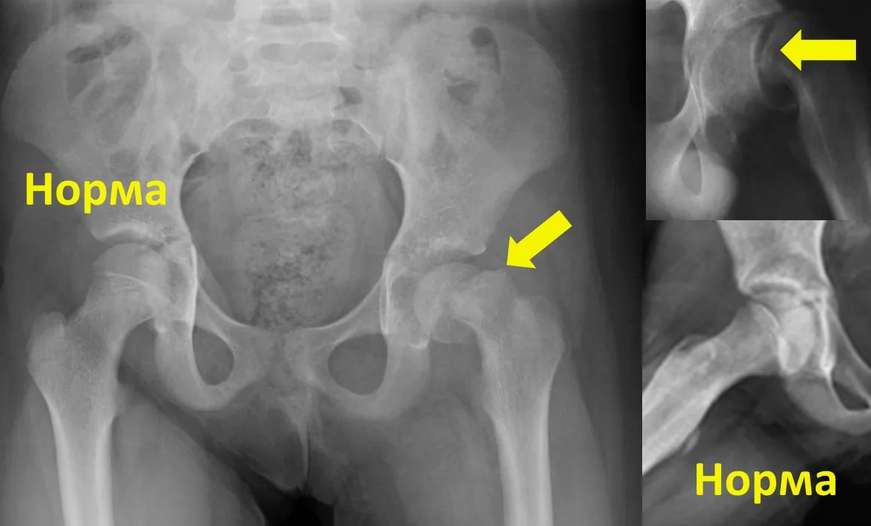

Рентгеновские снимки: Синовит тазобедренного сустава